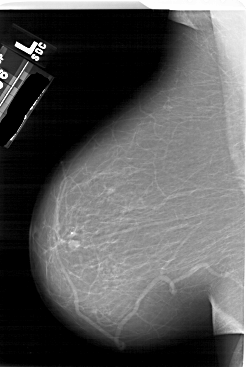

A_1623_1.RIGHT_MLO

RIGHT_MLO LINES 6496 PIXELS_PER_LINE 4501 BITS_PER_PIXEL 12 RESOLUTION 43.5 OVERLAY